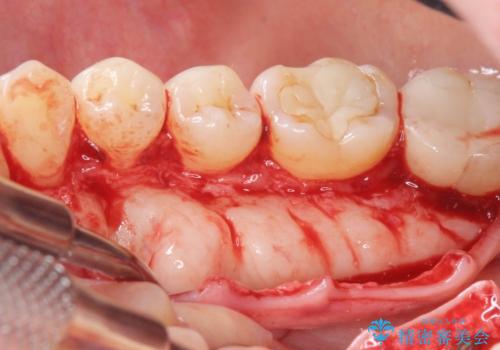

発音の邪魔となる骨隆起の除去

- 徐々に大きくなってきた骨隆起の除去を希望され来院されました。

下顎隆起を切除することで舌を収めるスペースを確保し発音のしやすさの向上を図ります。

手術は約1時間弱で終了し、術後もほとんど腫れは出ません。